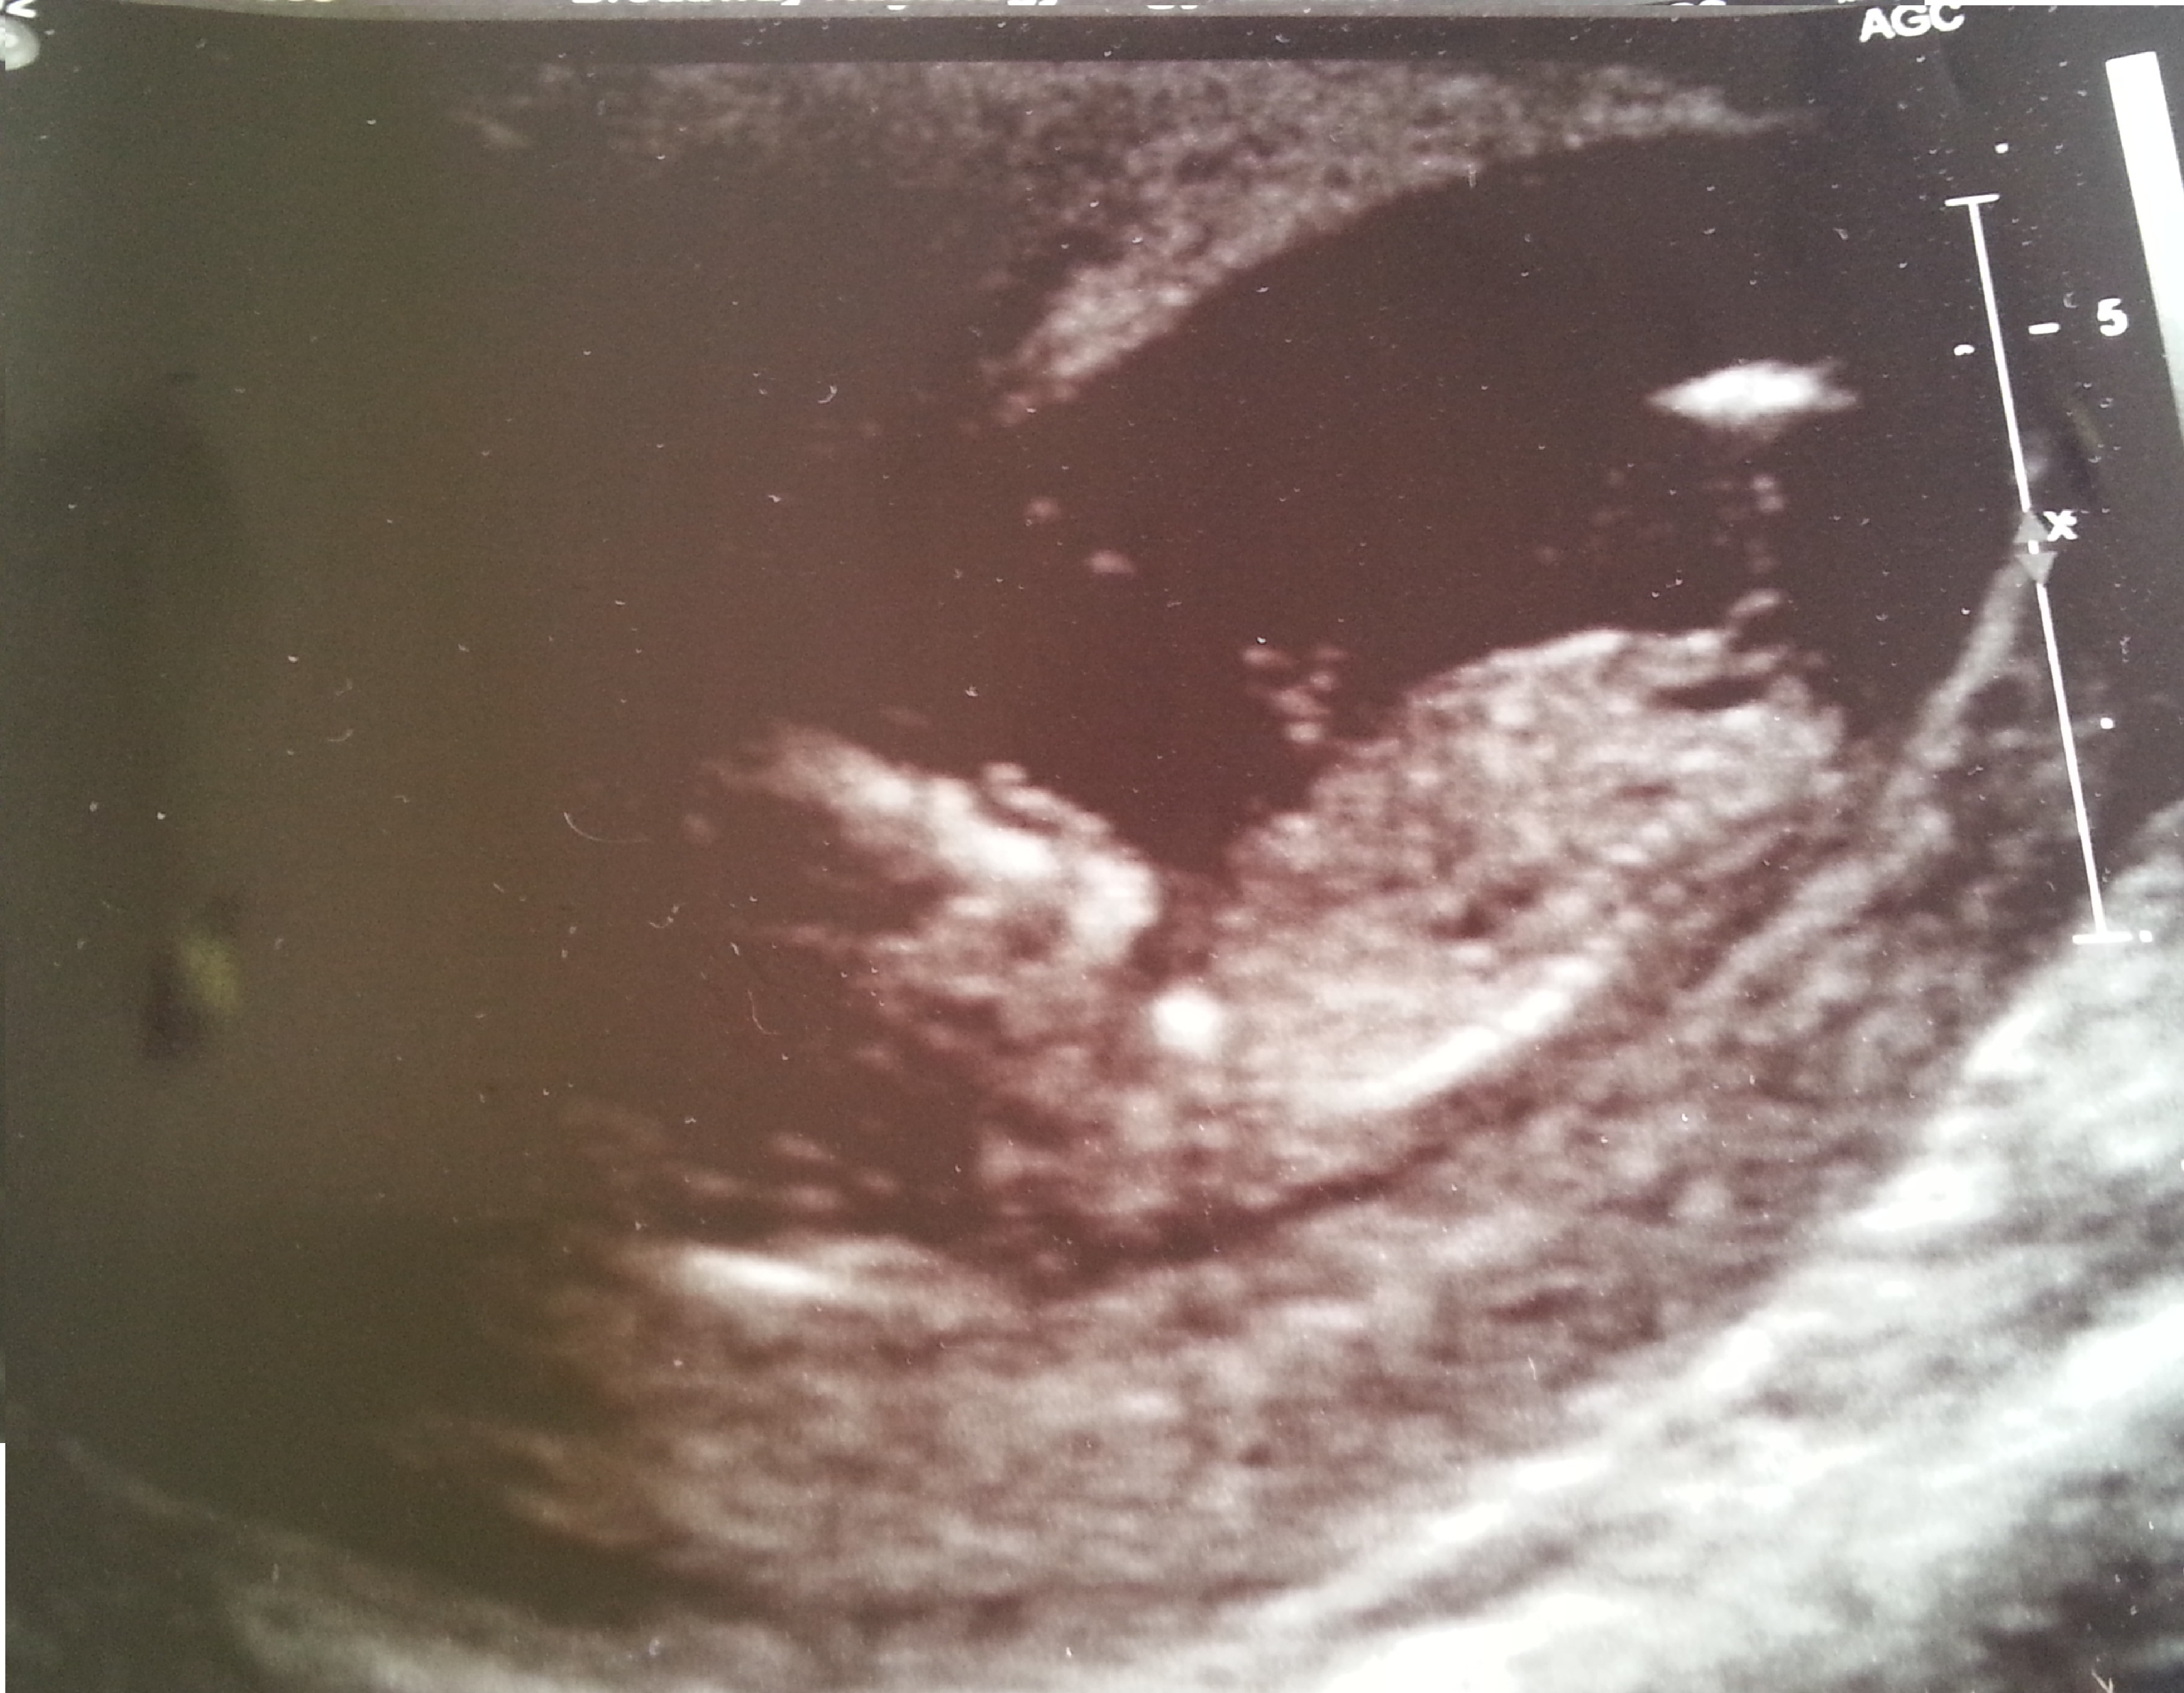

I've tried to resize the images.

And another. I hope this is clearer. Attachment 7310

In the last photo it looks like there's a nub leaning upwards. I'd guess a boy if that is indeed the nub.

I actually thought it looked like a girl :)